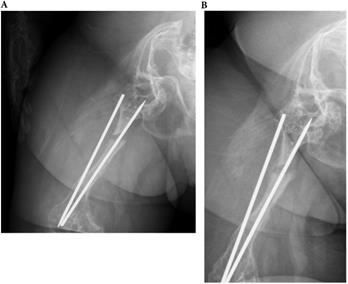

Figure 5

A 23-year-old female with type 4 OI had left distal femoral fracture with intramedullary nailing treatment in July 2016, which resulted in union. (a) Two weeks after operation (b) Follow up in July 2017.

Int J Med Sci Image

Influence of treatment on healing rate

In OI type 4, 2 of 5 (40.0%) fractures resulted in non-union. All two patients with type 4 OI who were conservatively treated with OI had shaft fractures resulting in non-unions. Three other patients with type 4 were surgically treated for shaft fractures. All resulted in union (2 IN, 1 PF) (Figures 3, 4, 5). In patients with OI with type 1 OI, 1 of 4 (25.0%) fractures resulted in non-union (Figure 6), for type 3, 1 of 6 (16.7%) fractures resulted in non-union (Figure 7).